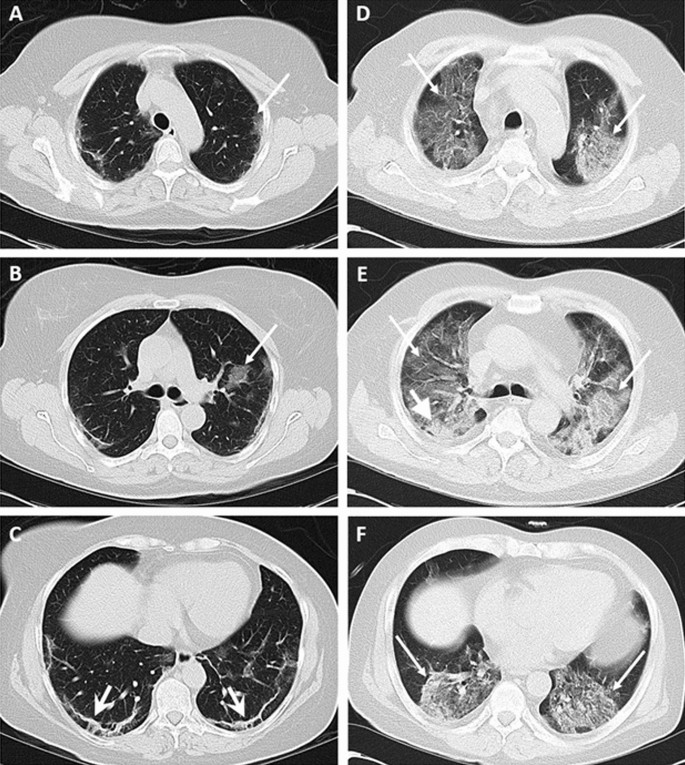

“a – c Um homem de 55 anos apresentou histórico de 5 dias de febre e tosse seca sem qualquer comorbidade [nível de 25(OH)D foi de 40 ng/mL] com pontuação de envolvimento de tomografia computadorizada (TC) pulmonar inicial de oito/24. Na admissão, as imagens de TC mostraram opacidades em vidro fosco (GGO) irregulares sutis (setas longas) predominantemente nas zonas superiores e padrão reticular (setas largas) nas zonas inferiores. O paciente teve alta após 6 dias.

d – f Um homem de 54 anos com histórico de 4 dias de febre, tosse seca e dispneia e nenhuma outra comorbidade [o nível de 25(OH)D era 7 ng/mL]. Escore de envolvimento da TC de pulmão de noventa/24. Na admissão, as imagens de TC mostraram GGO difuso (setas longas) com leve alteração de consolidação (seta na cabeça grossa) na zona média direita. O paciente morreu após 19 dias.”